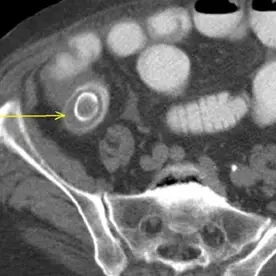

Die abdominale CT bestätigt den bereits klinisch geäußerten Verdacht auf einen Gallensteinileus. Es besteht ein mechanischer Dünndarmileus durch den obstruierenden großen Gallenstein prävalvulär an der Bauhin'schen Klappe sowie eine Aerobilie. Die Aerobilie kann sowohl durch die bereits durchgeführte ERCP mit Stentanlage als auch durch die Gallensteinpermeation bedingt sein.

Das Erscheinungsbild entspricht der Rigler-Trias und ist besser zu erkennen als im Röntgenbild. Da nur eine Minderheit der Gallensteine verkalken (12,5 %) und ihre Dichte dem normalen Darminhalt ähnelt, kann man den Gallenstein leicht übersehen. Kurz vor dem Übergang kann es zu einer Ausstülpung des Darms kommen, was bei der Lokalisierung des Gallensteins hilfreich sein kann. In der Regel sind die Steine groß und messen mehrere Zentimeter (2-3 cm).

Außerdem ist oft die Stelle der Fistelbildung zu sehen. Diese tritt am häufigsten zwischen der Gallenblase und dem Duodenum auf.